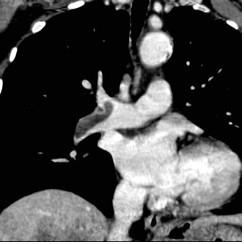

Isquemia mesentérica: Aguda y crónica